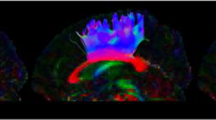

Among the output files generated by Freesurfer are image files containing masks of individually labeled neocortical and non-neocortical GM regions (Fischl et al. 2002). These image files were mapped back to native scanner space along with the T1-weighted image used for segmentation and resultant output files written to nifti format. Subsequent analyses requiring intra-subject co-registration of the GM masks, the T1-weighted images, and the DTI dataset collected from the same imaging session were performed using FSL v4.1.0 (Smith et al. 2004)(e.g. FMRIB’s Software Library, www.fmrib/ox.ac.uk/fsl). Minor head motion and eddy currents were corrected in the DTI series with the Eddy Current Correction tool included in FSL’s Diffusion Toolbox v2.0. Subsequently, skull-stripping and removal of non-brain tissue was performed using BET v2.1. FSL’s Linear Image Registration Tool v5.5 (FLIRT; (Jenkinson et al. 2002)) was used to perform a within subject inter-modal linear registration between each subject’s T1-weighted series (reference image) and corresponding non-diffusion-weighted images (b = 0) from the DTI dataset (see Fig. 1). The resultant transformation matrix, and calculation of its inverse, provided the basis for co-registering the GM masks obtained from Freesurfer’s analyses of the high-resolution T1-weighted images with each individual’s DTI dataset. The diffusion tensors were reconstructed using FSL’s DTIFIT tool within the Diffusion Toolbox. Quantitative measures of MD and FA were obtained from each study participant using regions circumscribed by the co-registered masks of the amygdala and hippocampus and command line utilities included with the FSL software package.

Co-registration of Freesurfer GM masks for the amygdala (red) and hippocampus (blue) with processed DTI dataset from one participant. The first row displays sagittal, coronal, and magnified axial views of the participant’s T1 image set with transparent overlays of GM masks for the amygdala and hippocampus in the left hemisphere